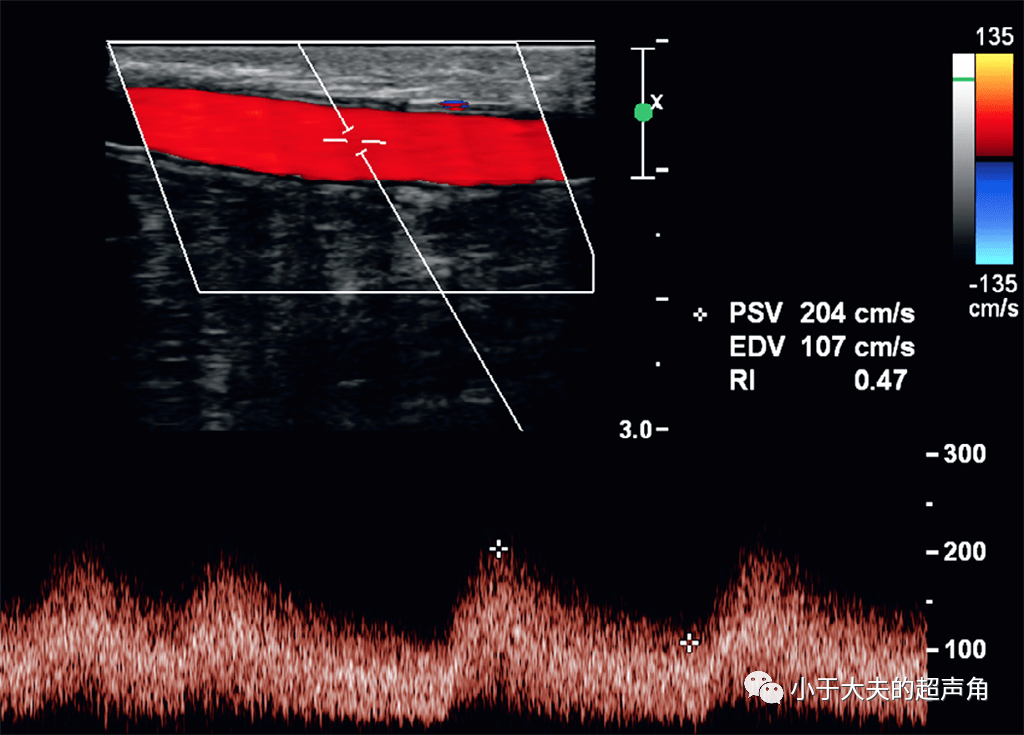

动静脉瘘频谱

这是浅静脉内的血流频谱,已经是动脉化的静脉频谱了,因为瘘口很大

图三:动静脉瘘频谱.